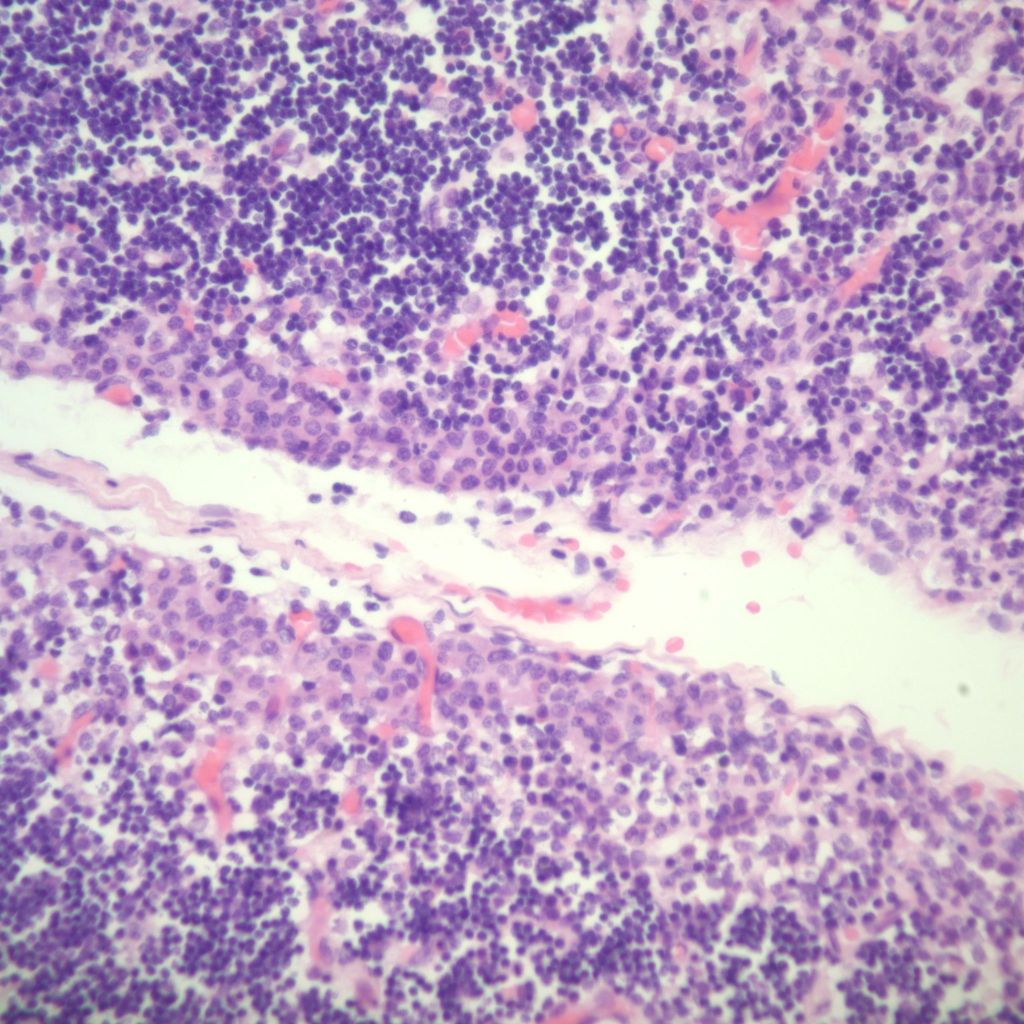

1. Petechial hemorrhages:

Petechial hemorrhages are usually scattered within the parenchyma, not just on the surface. (Fig 7,8)

They may be difficult to perceive in autolyzed tissue. Thymic petechiae have been associated with acute asphyxia in stillborn infants, such as with premature separation of the placenta[5, 6]. In this scenario, the petechiae are usually sparse, superficial, and as is also the case with thymic petechiae in SIDS, not on the cervical thymus. Larger, confluent hemorrhages in the thymus, often suggest a more systemic coagulation disorder. Thymic petechiae associated with asphyxia are often accompanied with other intrathoracic petechiae including on the visceral pleura and the epicardium. To interpret the meaning of these petechiae requires understanding the mechanism of petechial hemorrhage formation and then to relate that to the events that occur with acute intrauterine asphyxia.